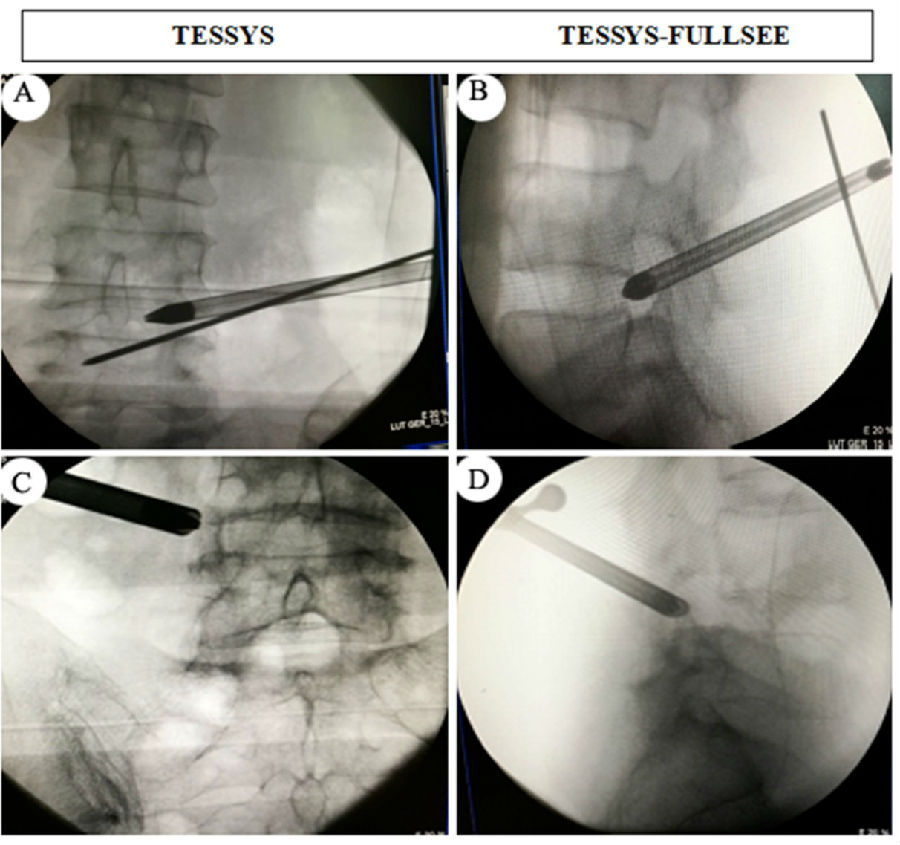

術(shù)中透視.

與傳統(tǒng)的TESSYS技術(shù)穿刺全程需要X線透視相比,我們采用的全麻下的TESSYS-FULLSEE椎間孔鏡技術(shù),術(shù)中常規(guī)只需透視一次,然后在內(nèi)鏡可視化操作下將孔鏡工作套管置入病變區(qū)域。該技術(shù)具有以下特點:1. 真正意義上的全內(nèi)鏡技術(shù),貫穿穿刺至髓核摘除全過程;2.術(shù)中透視少,僅在將通道置入椎間孔后透視正側(cè)位一次,對病人和醫(yī)護(hù)人員輻射少;3.整個手術(shù)操作在脊柱內(nèi)鏡監(jiān)視下進(jìn)行,不易損傷神經(jīng),安全性好;4.采用全麻,病人舒適度高;5.與傳統(tǒng)脊柱內(nèi)鏡技術(shù)相比,精準(zhǔn)程度更高,組織創(chuàng)傷更小,減壓更徹底,術(shù)后疼痛緩解更明顯;局麻下手術(shù),患者術(shù)中可能會出現(xiàn)因神經(jīng)根刺激和髓核摘除操作給患者造成難以忍受的劇烈疼痛,術(shù)中需要靜脈輔助強(qiáng)化藥物來麻醉患者;這些弊病,全麻下可以完全避免。